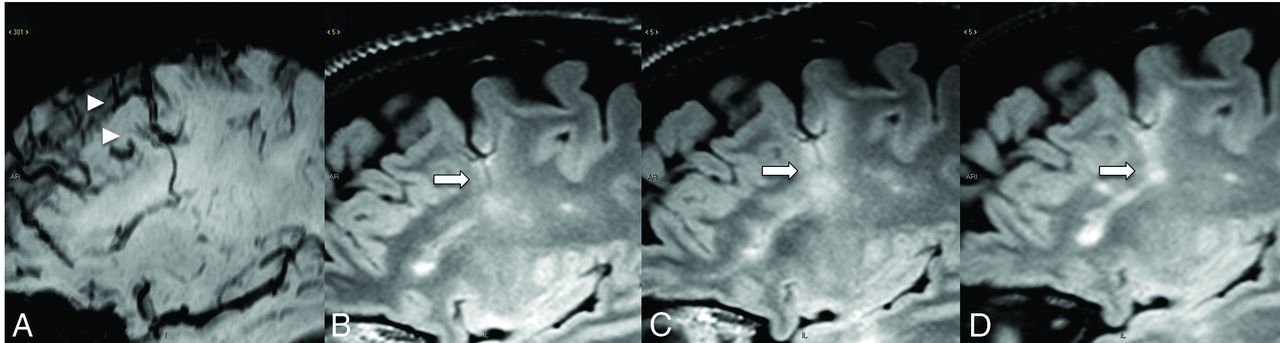

A patient with MS with an SWI (A) demonstrating a DVA. FLAIR at 6-month (B), 1-year (C), and 2-year (D) follow-up shows an enlarging demyelinating plaque (arrows) centered around the DVA.